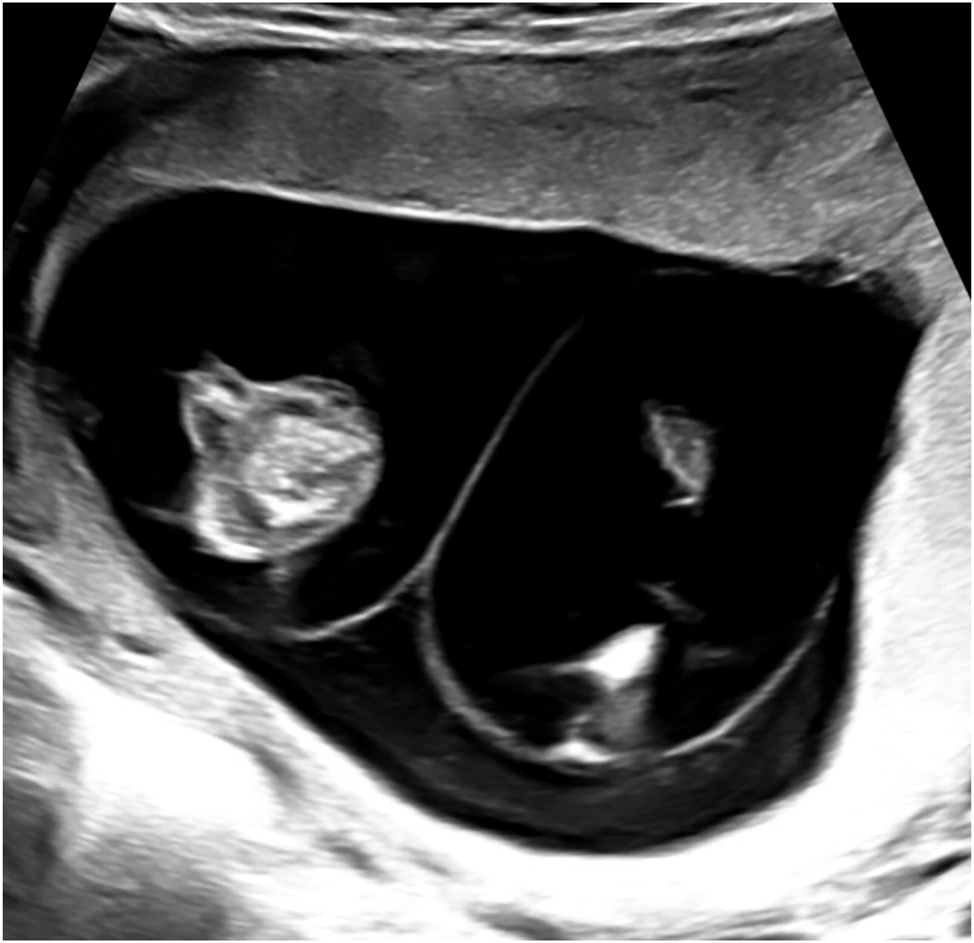

Twin-to-twin transfusion syndrome (TTTS) affects about 10 % of MCDA twin pregnancies and typically manifests between the 16th and 26th week of gestation [2]. It is sonographically defined by oligohydramnios in the donor and polyhydramnios in the recipient, with different cut-offs depending on gestational age. If the deepest vertical amniotic fluid pocket before 20 weeks of gestation meets the criteria of >8 cm in the recipient and <2 cm in the donor, this is referred to as Quintero stage 1 (Figure 2). After 20 weeks the threshold of >10 cm is used for polyhydramnios in the recipient [13], 14]. If such amniotic fluid discordance is accompanied by the absence of bladder filling in the donor, this is referred to as Quintero stage 2. Doppler sonography should be used to assess the hemodynamic stress on both fetuses and is also applied for staging according to Quintero. Typically, the recipient’s cardiac volume overload is reflected in abnormal flow patterns (absent or reversed flow in the a-wave) in the ductus venosus (Figure 3) or pulsatile flow in the umbilical vein, while the donor may present with absent or reversed end-diastolic flow in the umbilical artery. As soon as such signs of hemodynamic compromise occur, this is referred to as Quintero stage 3, although the stage progression does not necessarily have to occur in chronological order [13], 15]. If hemodynamic compromise progresses this can lead to fetal hydrops (Quintero Stage 4, Figure 3) or death (Quintero Stage 5). While the inclusion of further cardiovascular parameters can stratify additional characteristics of fetal pathophysiological changes, this does not improve the prediction of outcome after intrauterine interventions. Despite certain limitations [16], the Quintero stages remain the most practicable classification for TTTS [12], 13].

Sonographic image of TTTS (22 + 0 weeks) with polyhydramnios of 14 cm in the recipient (left) and oligohydramnios (1.6 cm) in the donor (right).